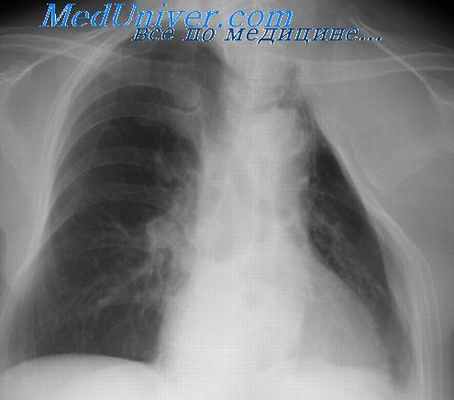

Клинические проявления острой эмпиемы зависят от распространенности гнойного процесса, вирулентности микрофлоры, степени деструкции легочной ткани, реактивности больного, а также от своевременности и полноценности проводимого лечения (Рис. 2.3.). В большинстве случаев заболевание протекает на фоне дыхательной и сердечно-сосудистой недостаточности, которые обусловлены полным или частичным спадением легкого, смещением средостения, сдавлением крупных сосудов и нарастающей эндогенной интоксикацией.

При объективном обследовании отмечается бледность кожи и слизистых оболочек, тахикардия, одышка. Грудная клетка на стороне поражения становится бочкообразной со сглаженными межреберьями. Перкуторно отмечается притупление легочного звука в нижних отделах и коробочный звук выше горизонтальной линии жидкости. Аускультативно – резкое ослабление или отсутствие дыхательных шумов. При закрытой эмпиеме, при отсутствии воздуха в плевральной полости и сращений, верхняя граница тупости соответствует линии Эллиаса-Дамуазо, а над зоной тупости отмечается тимпанический звук (признак Шкоды).

Рентгенологически на стороне эмпиемы определяется интенсивное затенение, смещение средостения в здоровую сторону. При пиопневмотораксе верхняя граница жидкости становятся горизонтальной. Над уровнем жидкости определяется воздушная полость. В зависимости от степени коллапса легкого различают ограниченный, субтотальный и тотальный пиопневмоторакс. При ограниченных эмпиемах плевры для уточнения формы, размеров, наличия бронхиальных свищей проводят плеврографию – введение водорастворимых контрастных веществ в полость эмпиемы с помощью пункции или через фистулу при наличии плеврокожного свища.